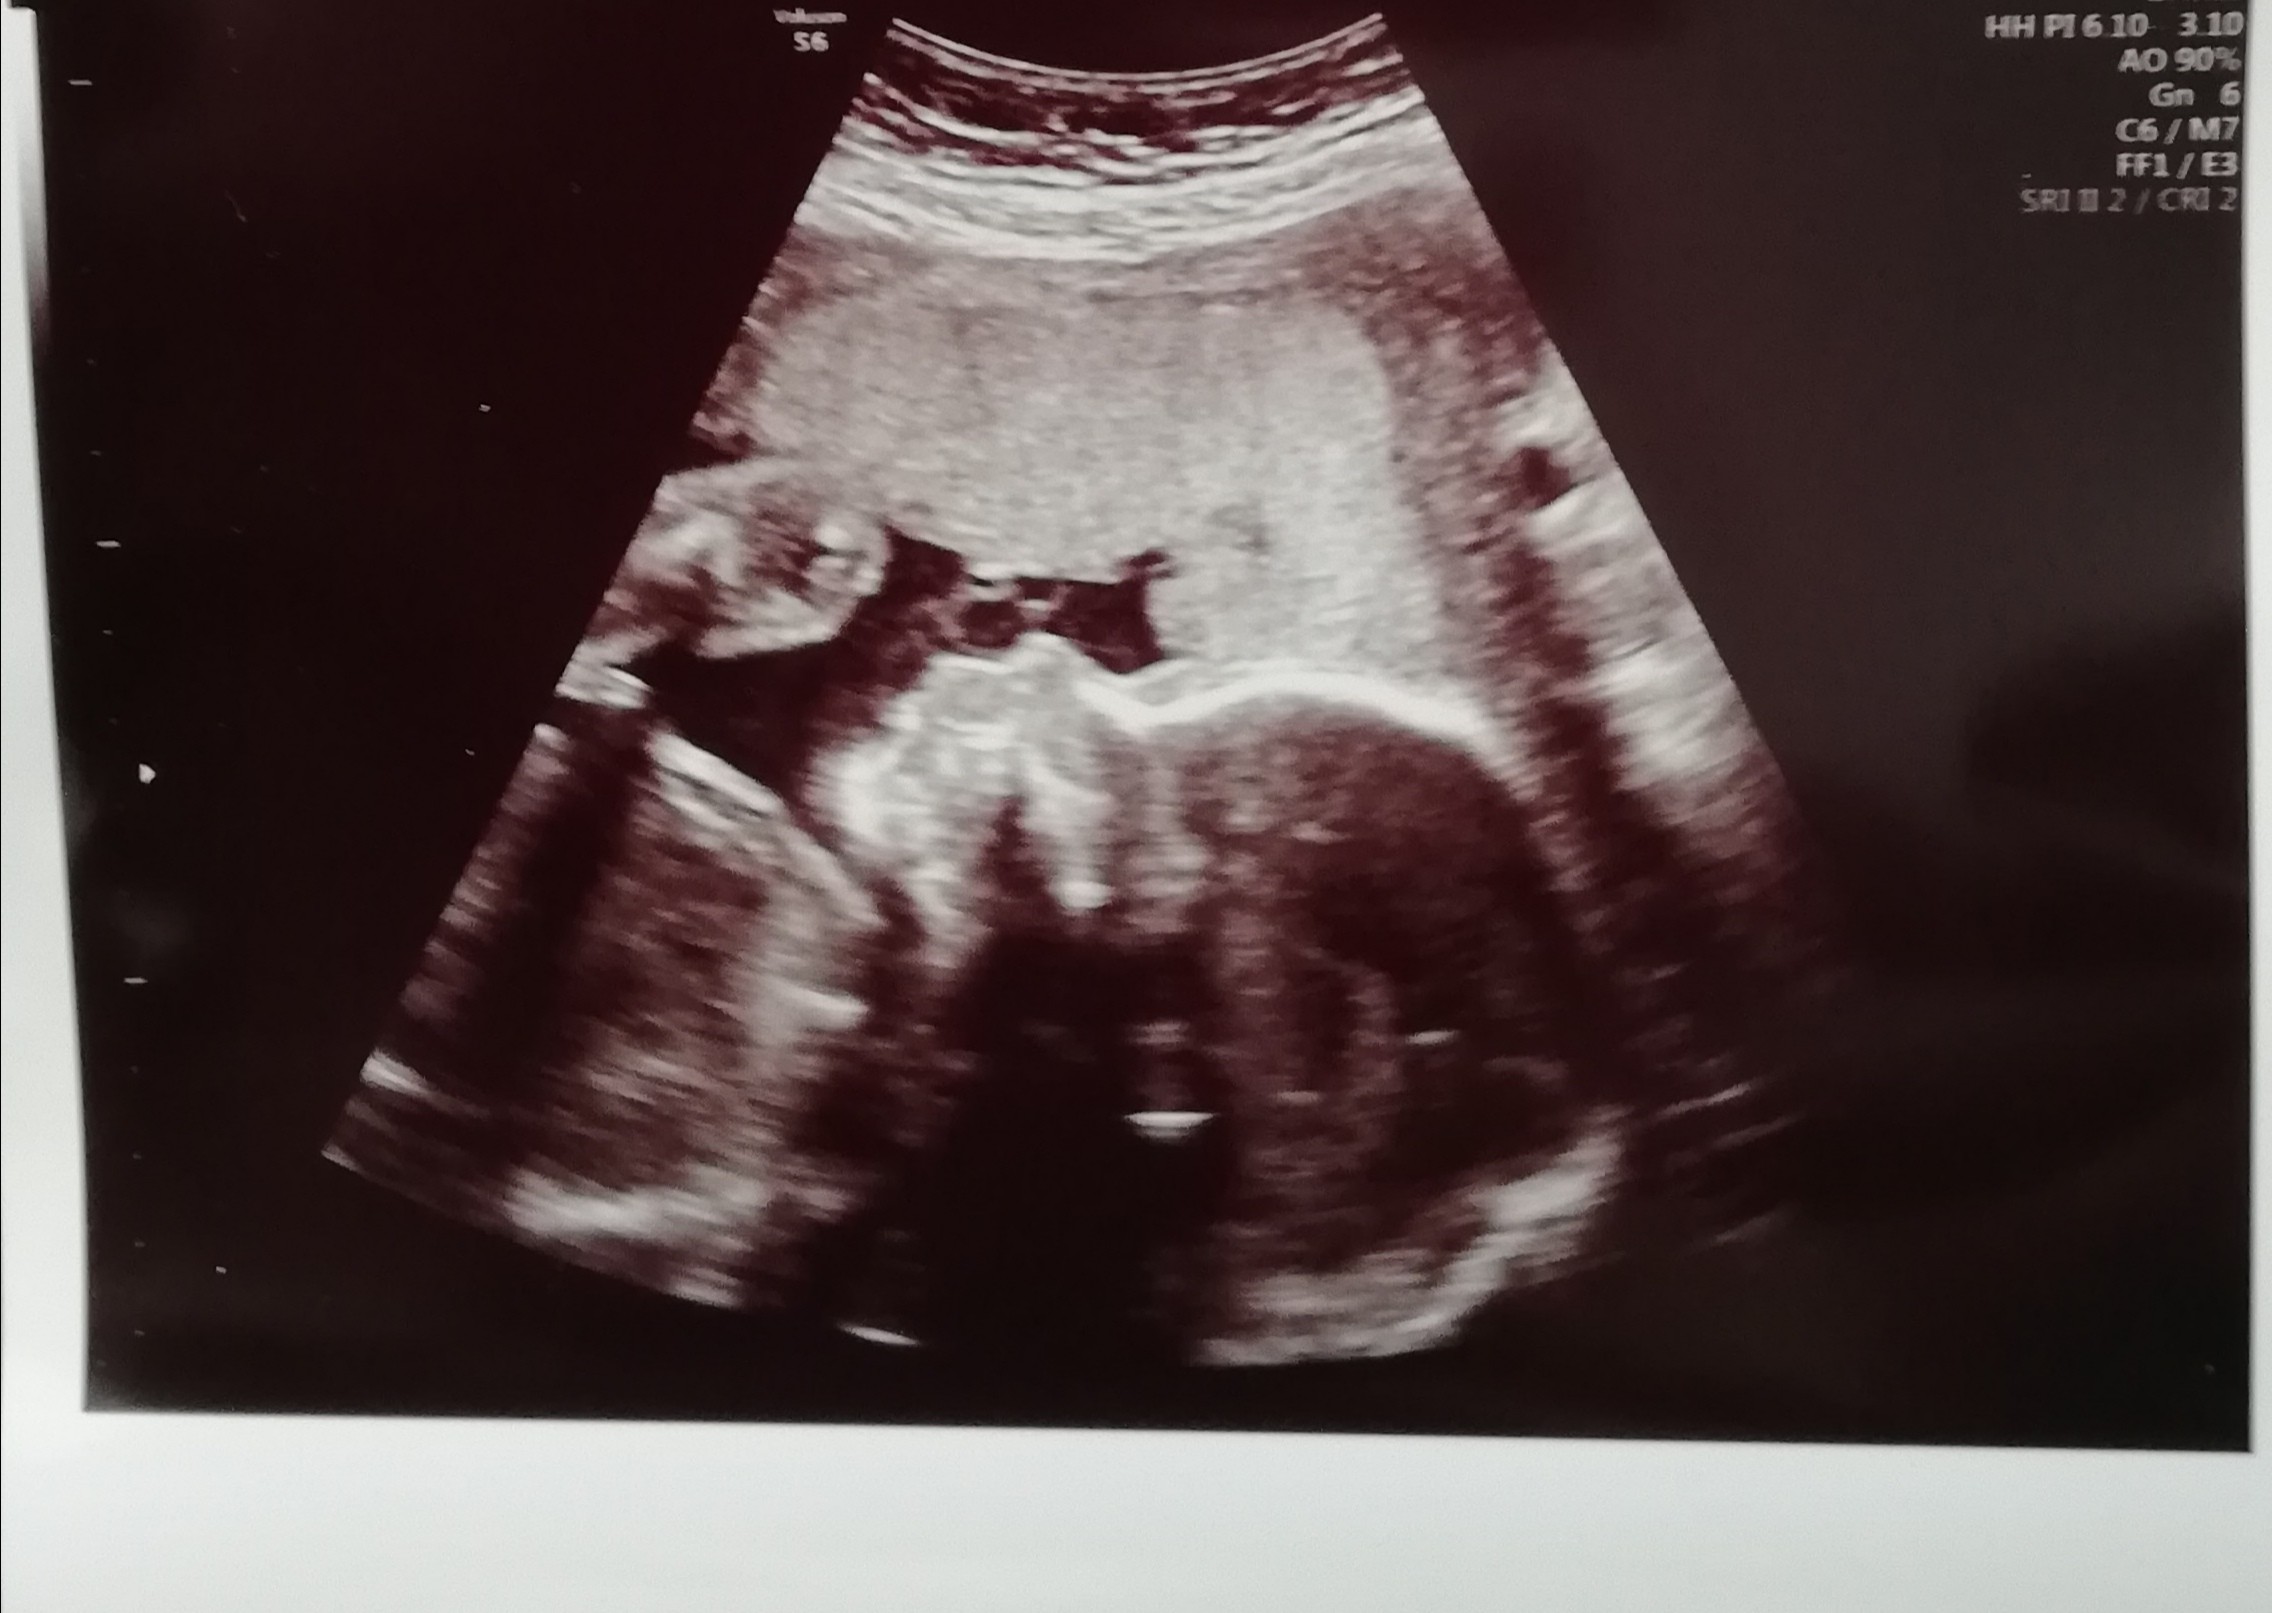

Onka dacie z maluszkiem radę! Będzie dobrze! Jesteś ‚pod okiem’ specjalistów, trzeba myśleć tylko pozytywnie ❤ My dziś w końcu się zobaczyliśmy po 2 miesięcznej przerwie z maluszkiem- tj. Ja widziałam na USG ale mam wspaniałą doktor i pozwoliła na filmowanie USG, żeby mąż zobaczył